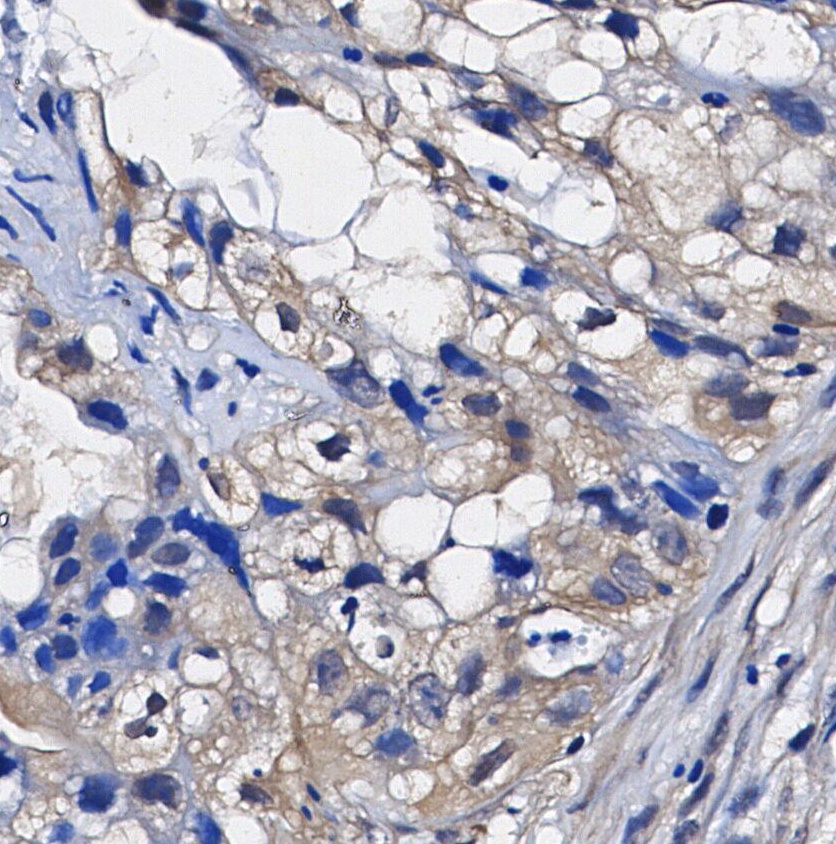

• Immunohistochemical analysis of formalin fixed paraffin embedded human Lung adenocarcinoma tissue with F1014 at 1/100 dilution.